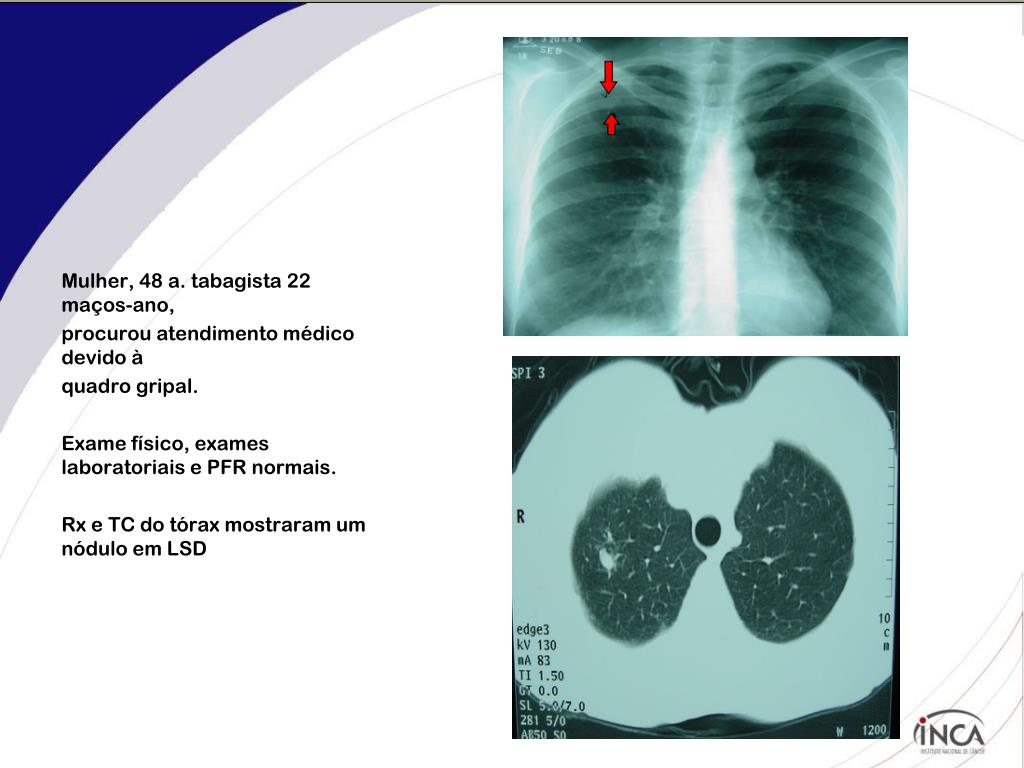

2. Mulher, 48 a. tabagista 22 maços-ano, procurou atendimento médico devido à quadro gripal. Exame físico, exames laboratoriais e PFR normais. Rx e TC do tórax mostraram um nódulo em LSD